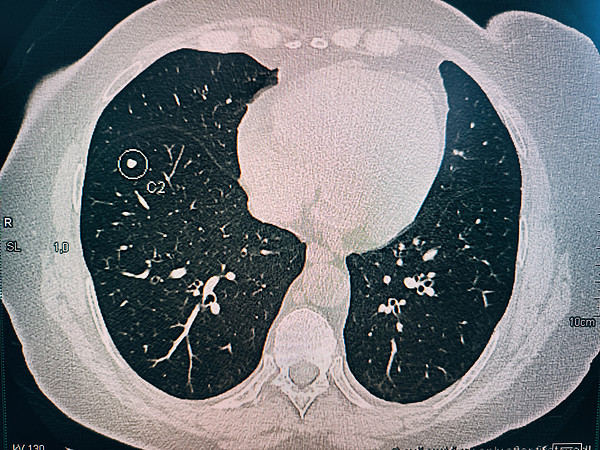

IMG_20250321_165010.